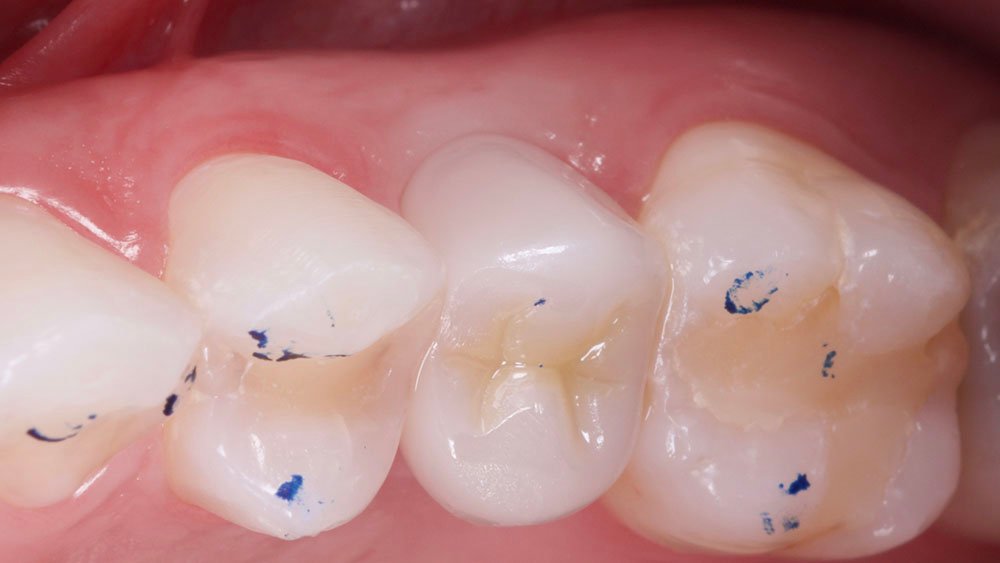

Durante a anamnese, a paciente apresentou um bom estado de saúde geral e não relatou nenhum dado médico relevante que impossibilitasse o tratamento. No exame físico intraoral, observou uma boa condição de saúde bucal, notando-se apenas a ausência do elemento 15 com uma depressão óssea no vestibular. Dessa forma, objetivou-se um plano de tratamento baseado na utilização da técnica de rolo modificada e colocação de dente provisório.

Os nervos alveolares superiores anterior, médio e o palatino maior foram anestesiados com dois tubetes de Cloridrato de Mepivacaína 2% (Cristália Produtos Químicos Farmacêuticos Ltda., São Paulo-Brasil). Com o auxílio de uma lâmina 15C (Syann Morton – Cód.11810 (HOS11810A)), foi realizada uma incisão ligeiramente palatinizada em retalho dividido, paralela ao tecido ósseo palatino, de modo a separar a porção mais epitelial do tecido conjuntivo palatino (aproximadamente 2 mm) da porção mais profunda (aproximadamente 3 mm), para que em seguida, uma segunda incisão no tecido palatino (abaixo do alçapão formado pela primeira incisão) pudesse liberar essa porção mais profunda (juntamente a periósteo) e a mesma seja rotacionada para a vestibular do defeito. Na sequência, outras duas incisões em retalho total (até periósteo) foram realizadas de modo a dar a forma das futuras papilas proximais. Uma última incisão superficial foi realizada na porção oclusal do defeito com a finalidade de desepitelização para que o tecido oclusal também fosse rotacionando para a vestibular. Para o descolamento do enxerto e mucosa vestibular foram utilizadas curetas Molt (Supremo Instrumentais).

Com auxílio de uma pinça porta agulha Castroviejo e pinça Dietrich 16 (Supremo Instrumentais), e fio de sutura Micro PTFE 5.0 (GolnitTM, Ucrânia-Europa – MICROSUTURE), foi realizado a sutura da região com pontos do tipo colchoeiro horizontal, posicionando o rolo dentro do retalho, tipo envelope na região vestibular.